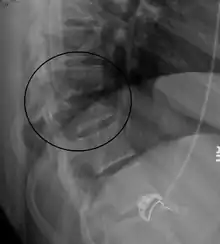

![]() كسر تشانس عند T10 وكسر T9 بسبب حِزام المَقعد خلال تَصَادُم سيَّارة. كسر تشانس عند T10 وكسر T9 بسبب حِزام المَقعد خلال تَصَادُم سيَّارة. | |

السبب عادةً هو حادِث مُروريّ في مُواجَهة مُباشرة بحيث يكون الشَّخص المُتأذِّي مُرتديًا حزام أمان،[2] كأن تُضرَب في بطنك بواسطة شيء ما كشجرة أو أيّ وقوع ينتج عنه هذا النَّمط من الكسر.[12][10] يحدث فيه غالبًا تمزُّق الأعمدة الثلاثة لفقرات الجسم (الأماميَّة والوسطى والخلفيَّة)،[8][7] وأكثر المناكق شيوعًا هي الشَّوكة الصدريَّة السُّفلى والقطنيَّة العُليا.[7] يُنصَح بالتَفَرُّس المَقْطَعِيّ المُحَوسَب كجزء من العمل التشخيصيّ للتحقُّق من وجود أيّ إصابات بَطنيَّة مُحتملة،[6] وغالبًا ما يكون الكسر غير ثابتٍ.[1]

قد يُشَك بكسر تشانس على صورة أَشِعَّة سينيَّة واضحة إذا كان النَّاتِئان الشَّوكِيَّان مُبتعدان كثيرًا عن بعضهما.[10]